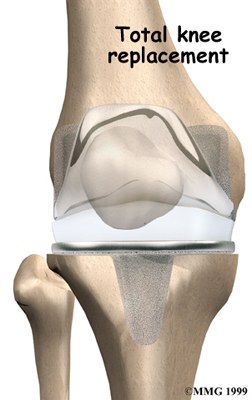

Artificial Knee Replacement

An artificial knee replacement is the ultimate solution for advanced knee OA.

Surgeons prefer not to put a new knee joint in patients younger than 60. This is because younger patients are generally more active and might put too much stress on the joint, causing it to loosen or even crack. A revision surgery to replace a damaged prosthesis is harder to do, has more possible complications, and is usually less successful than a first-time joint replacement surgery.

Related Document: FYZICAL Hendersonville TN's Guide to Artificial Joint Replacement of the Knee